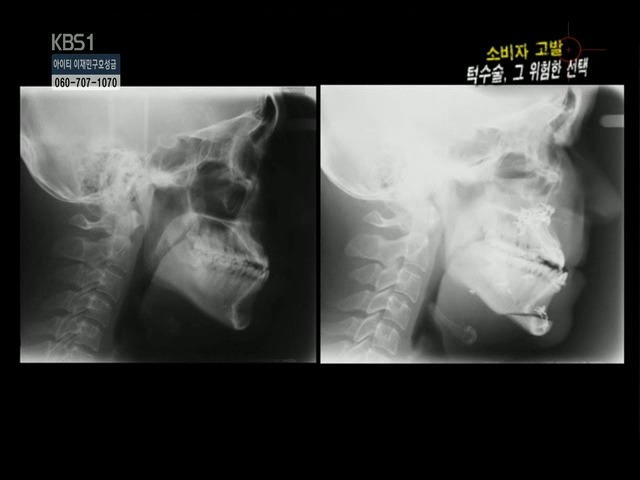

수술전 수술후

아까 위에서 나온 양악수술 부작용 오빠의 수술전 내 X-ray사진.

여기서 뭘 봐야하는지 알아??

일단 나랑 저 오빠 모두 주걱턱인것과, 윗턱 치아의 각도를 봐봐.

둘 다 비슷하지?

이건 나랑 이 오빠가 주걱턱이라 그런건데,

원래 정상인의 각도는 95도? 이정도 일거야. 거의 직각에 가까운.

근데 나랑 저 오빠는 60도정도밖에안되지??

저 오빠의 부작용은 아마 저기서 거의 다 왔을거야.

윗 설멍처럼, 양악수술은 윗턱을 잘라서 먼저 집어넣은다음에,

아랫턱을 윗턱에 맞게 잘라서 넣는거야.

수술할 때 윗턱때문에 거의 좌지우지한다고 볼 수있어.

근데 저 오빠는 윗이빨이 첨부터 누워있잖아?

정상각도에 맞춰서 한게 아니라

이미 잘못된 윗턱을 가진 상태로 수술을 하니 잘못될 수밖에.

저런 경우는 교정을 먼저 들어가서

교정으로 윗이빨을 세워준다음에 수술을하지.

아마 저 오빠는 교정 먼저 했다면 양악 할 필요도 없었을거야.

교정하고서 하악 수술만해도 정상이 될 수 있었을텐데.

보면 나보다 주걱턱이 덜 심하잖아.